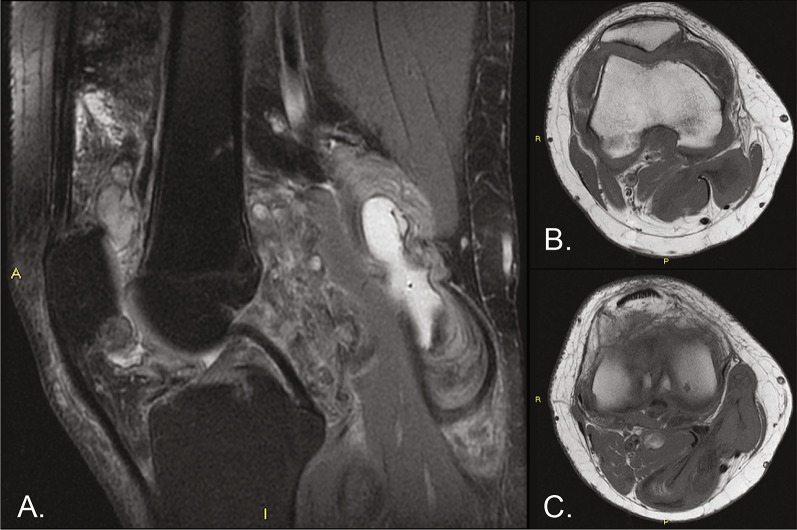

Case description: A 32-year-old man presented with intra-articular diffuse TGCT with pain and received noncurative treatment for 5 years (2014-2019). In 2019, the patient was found to have extensive disease accompanied by pain and limited range of motion. The patient's case was presented to a sarcoma multidisciplinary tumor board, who determined that surgery would cause significant morbidity and macroscopic residual tumor. As a result of the extent of disease, young age, and otherwise good health, treatment with pexidartinib was started through a compassionate use program at 800 mg/day. After dose reductions to pexidartinib at 400 mg/day and then 200 mg/day as a result of creatine phosphokinase elevations, the patient achieved a complete response after 2 years of treatment; pain was reduced and mobility was restored. The patient reported no side effects related to pexidartinib treatment. Treatment was stopped in 2022 for future family planning. After pexidartinib therapy was interrupted, the patient's wife had a successful pregnancy and delivery; however, the disease showed a slow but constant clinical deterioration, with a reduction in the range of movement of the affected knee and an apparent increase in widespread TGCT nodules.

Abstract Image